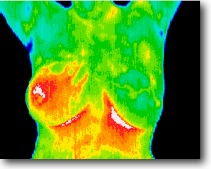

Red is warmer and blue is cooler

Thermography is a non-invasive diagnostic technique that converts infrared radiation emitted from the skin surface into electrical impulses that are visualized in color. The spectrum of colors indicates an increase or decrease in the amount of infrared radiation being emitted from the body surface. Medical Thermography can graphically display and record the subjective feeling of pain by objectively displaying the changes in skin surface temperature that are produced by pain states. Medical Thermography’s major clinical value is in its high sensitivity to pathology in the vascular, muscular, neural and skeletal systems and as such can contribute

to a diagnosis by the clinician.